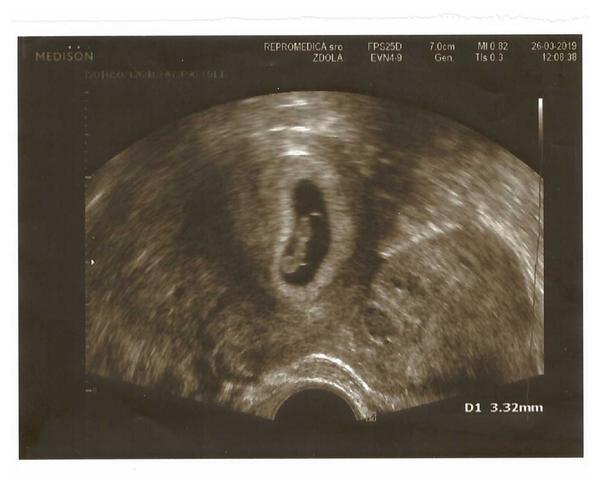

Ahojte baby... tak stalo sa to, čo som nečakala 🙂 namiesto kyretu sa bábo v gestačnom vaku objavilo 🙂 minulý týždeň plač a tento týždeň radosť... 7tt+4d a má cez 9mm a tlče mu aj srdiečko 🙂 Takže veľké prekvapenie 🙂 Už len dúfať, nech to tak aj vydrží... Držím Vám babeny všetkým palce... nech sa aj vám zadarí hneď na prvý pokus 🙂

@susangha Gratulujeeem 🙂 . Ja som ti taaaak strasne drzala palce, tesim sa velmi, velmi, velmi 🎉! Inac ja som bola vcera na kontrole, to som mala tiez 7+4 a velkost 9,3 mm 🙂 . Tak sme narovnako